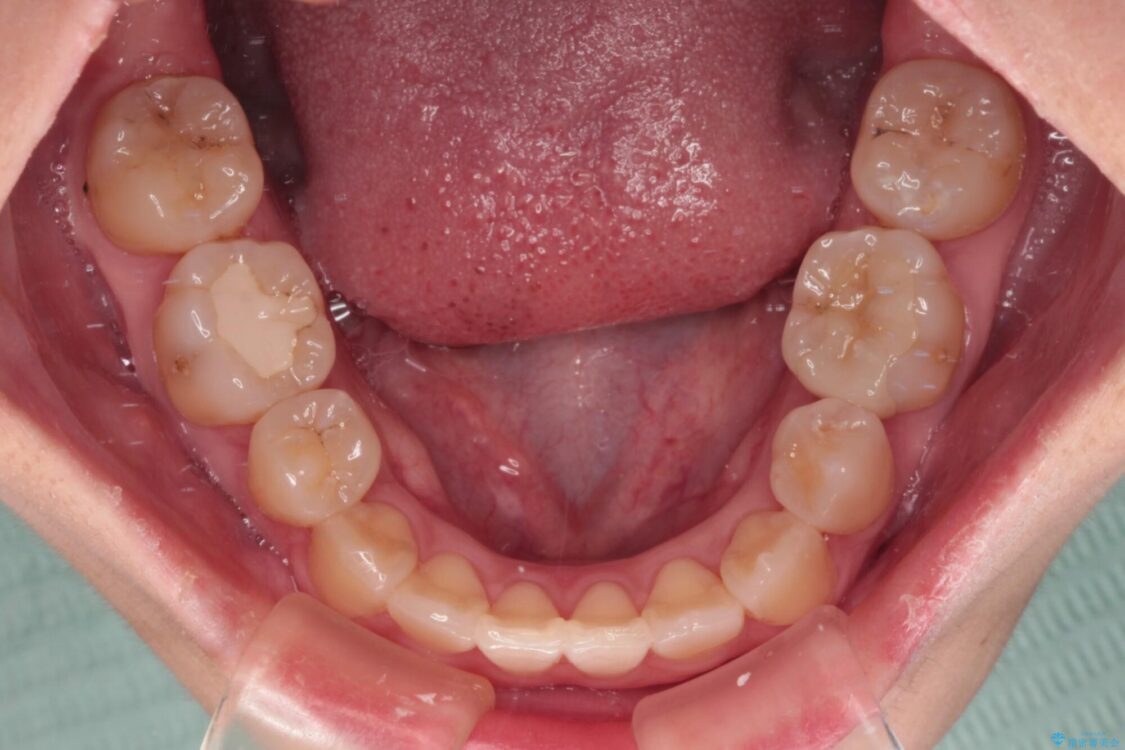

治療前

• 虫歯治療ついでに歯並びの後戻りを改善 インビザラインによる矯正治療 治療前画像

上顎親知らず周辺の炎症と、神経組織の失活した歯の炎症による痛みが認められたため、親知らずの抜歯と根管治療を行いました。

根管治療を行った歯はクラウンによる補綴治療が必要となりますが、高校生の頃に行った矯正治療の後戻りも気になるとのことで、補綴治療を行う前に矯正治療を行うこととしました。

後戻りは軽度であり、インビザラインにて歯列を整え、その後にオールセラミッククラウンにて補綴治療を行うこととしました。